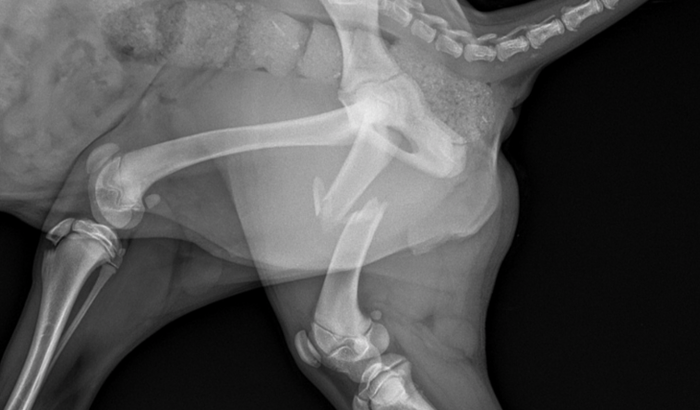

Mas um carro atropelou ela. Teve fratura no femur, deslocamento na articulação da pata dianteira e precisa de uma cirurgia e volocar pinos. Além disso está com hematoma no rim e esta sendo medicada com antibióticos e antiinflamatorios.

Não conseguimos atendimento pra ela em nenhuma ONG. Tivemos um gasto de R$ 1.600 reais com consulta, raio X, ultrassom, imobilizacao e remédios. Mas não temos condições de arcar com a cirurgia.